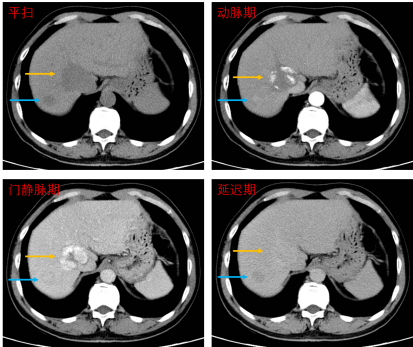

(某患者腹部平扫CT示两处低密度病灶,增强扫描确诊大病灶为良性血管瘤(黄箭),小病灶为肝癌(蓝箭)。)

这是另一例患者的腹部平扫CT图像,肝脏上有两处低密度病变,但性质尚不能确定。进一步行增强扫描,发现两处病变的强化方式不同,大病灶呈“快进慢出”、向心渐进性强化,诊断为良性血管瘤,小病灶呈“快进快出”强化,诊断为肝癌。说明在平扫CT上密度相似的病变,本质可能天差地别。磁共振也是类似原理。因此当平扫发现可疑病变或难以定性时,增强扫描就是为了更精准诊断,避免漏诊误诊。